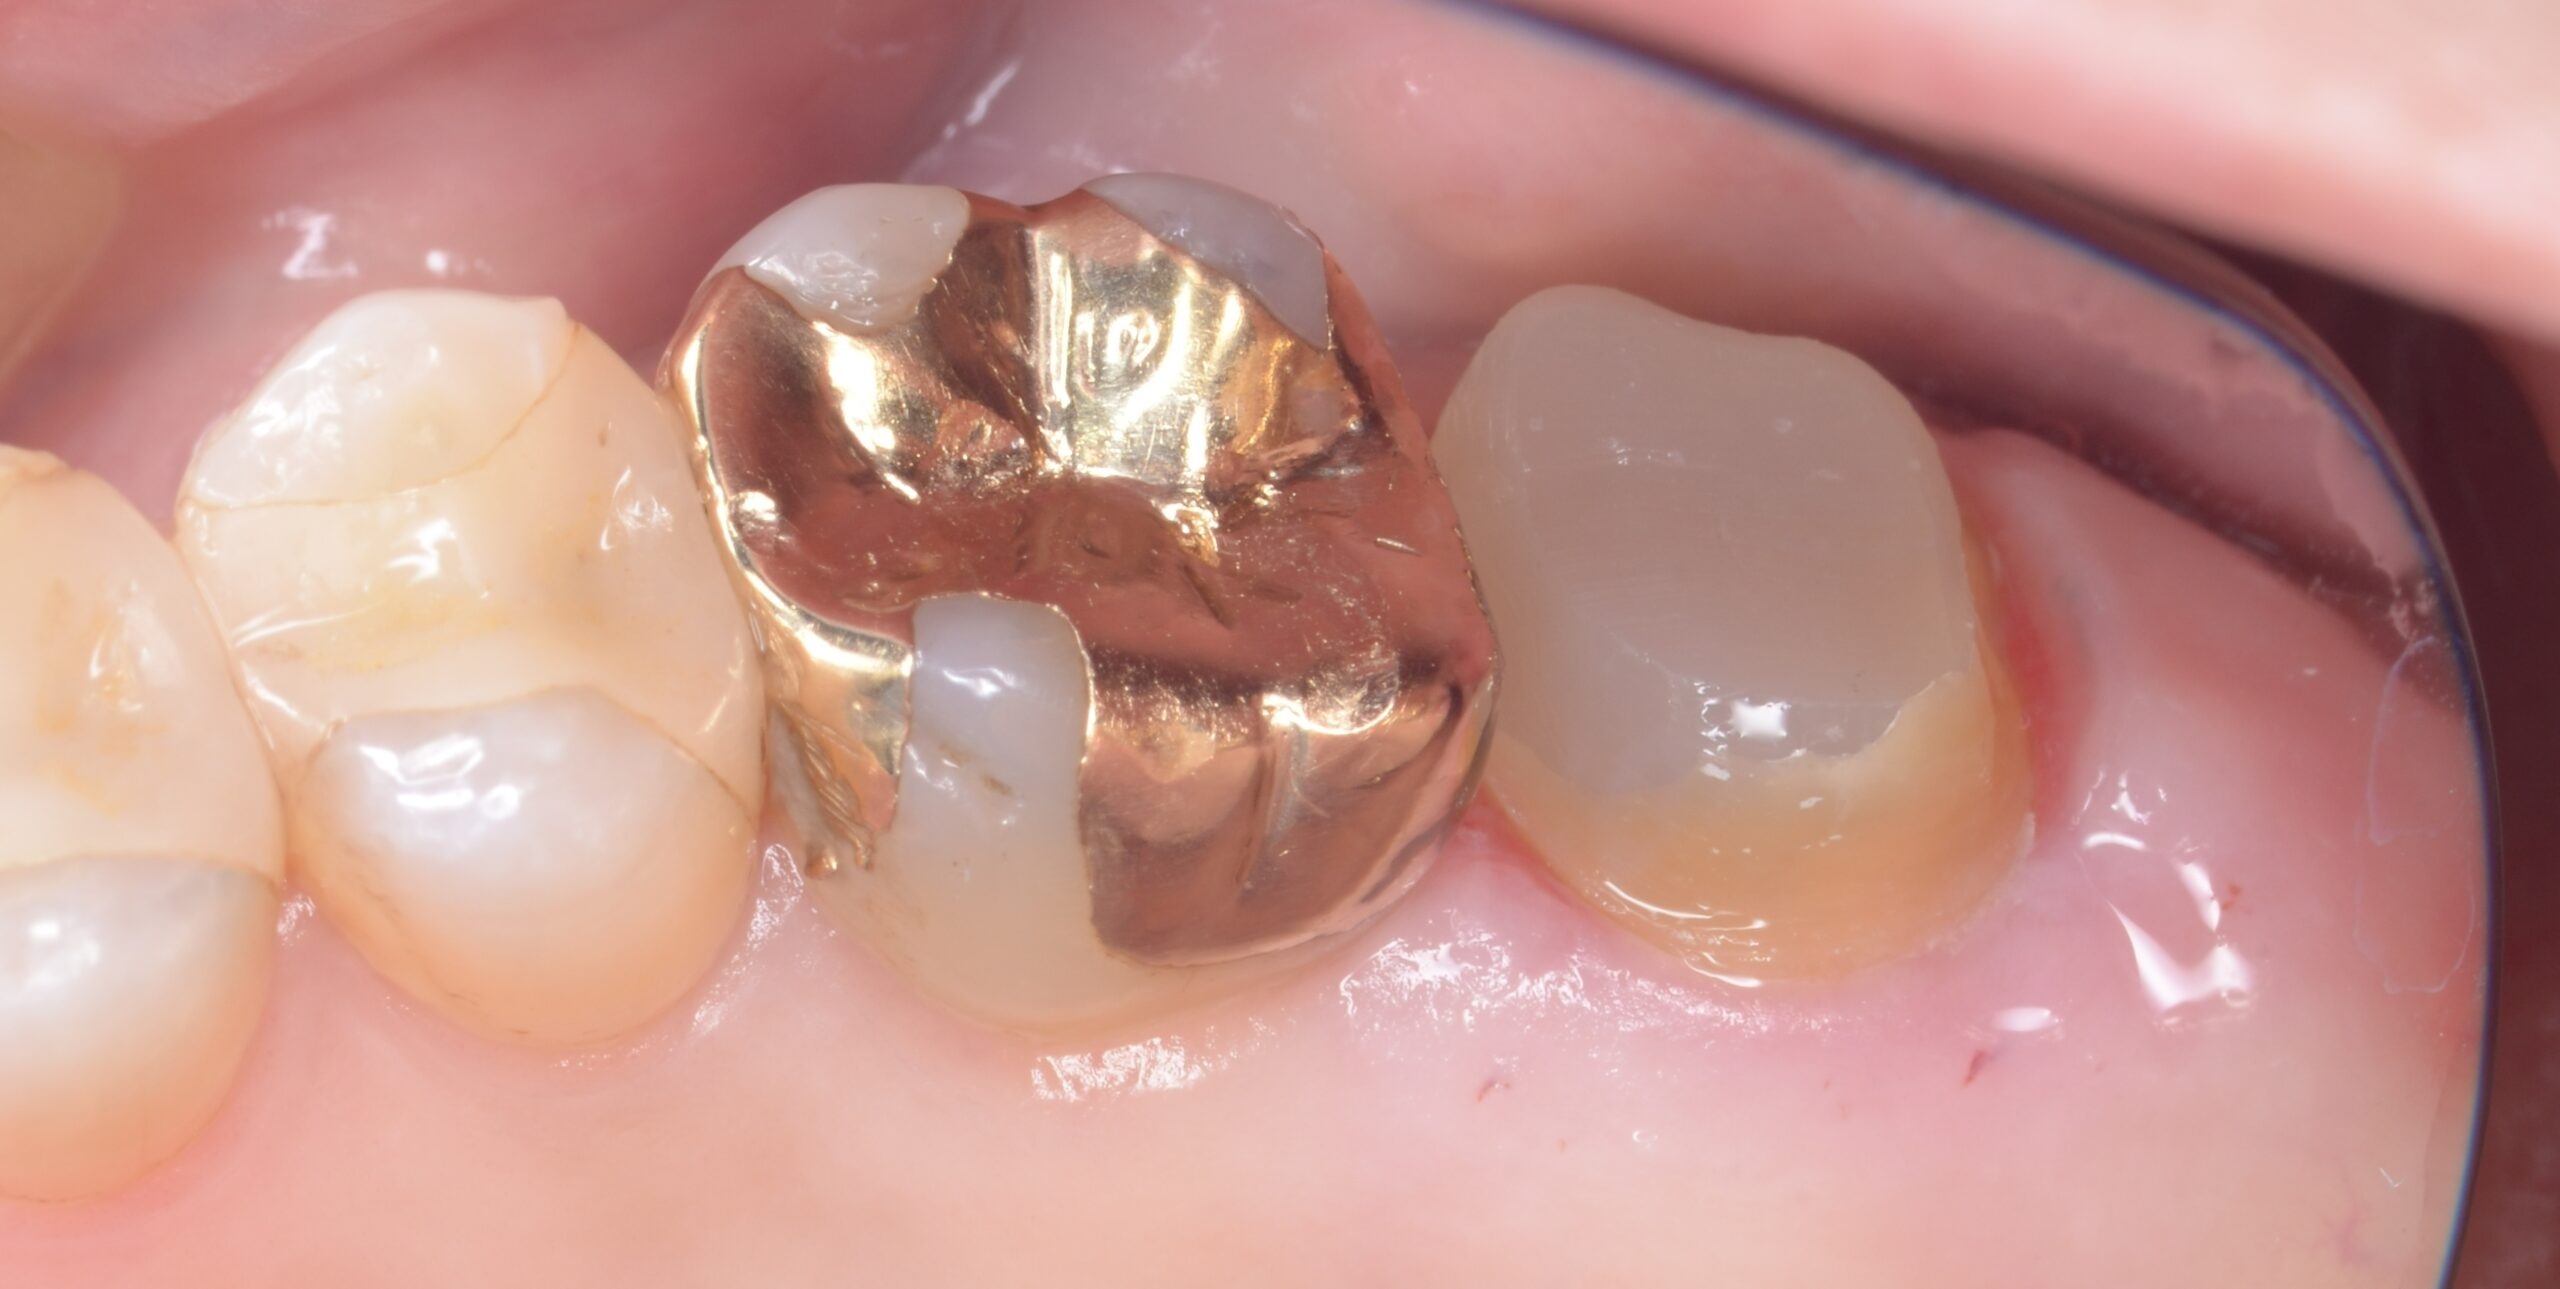

【歯周病治療】右上7番ディスタルウェッジ,オールセラミッククラウン

before

患者は右上臼歯部の歯肉腫脹および清掃困難を主訴として来院した。口腔内診査の結果、右上第二大臼歯遠心部に歯肉の肥厚およびポケットの残存が認められた。特に遠心部では歯肉形態の過剰により清掃性が低下しており、慢性的な炎症が持続している状態であった。

また、右上第一大臼歯および第二大臼歯には既存修復物が認められ、マージン適合および形態の問題からプラークコントロールが困難な状況であった。